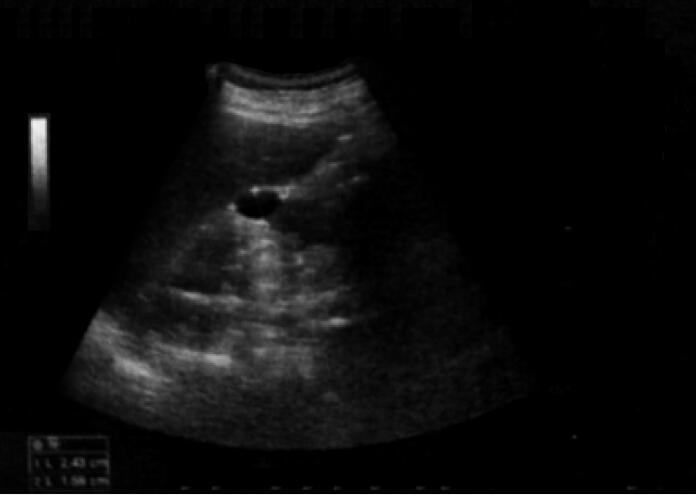

病情变化:住院第9天患者突发言语不清,左侧肢体麻木无力,腹痛,症状持续不缓解。影像学检查提示脾梗死(图3),双侧外囊区、基底节区、左侧额叶区腔隙性脑梗死。心脏超声考虑人工瓣狭窄,二尖瓣少量反流(图4)。

图3 第9天腹部彩超结果

脾厚约5.2cm,包膜光滑,完整,实质回声欠均匀,于下极实质见约7.9cm×3.9cm的低回声,边界欠清晰,CDFI:低回声内部未见明确血流信号。脾大、脾内异常低回声考虑梗死